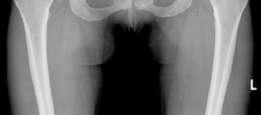

The radiographic evaluation of the dysplastic hip requires a highly standardized and rigorous protocol to accurately quantify the three-dimensional deformity. The initial assessment begins with a standing anteroposterior (AP) radiograph of the pelvis. In this patient, the AP view immediately reveals the hallmark signs of DDH: decreased anterolateral coverage of the femoral head and a broken Shenton line. The broken Shenton line—a step-off between the medial border of the femoral neck and the inferior border of the superior pubic ramus—indicates proximal and lateral migration of the femoral head due to structural instability. Furthermore, we observe an increased Tönnis angle (acetabular inclination) and a significantly reduced Lateral Center Edge Angle (LCEA) of Wiberg, confirming the diagnosis of severe lateral uncoverage.

The most critical functional radiograph in our preoperative workup is the AP Abduction view (often taken with the hip in 20-30 degrees of abduction and slight internal rotation). This view simulates the mechanical effect of a periacetabular osteotomy by effectively "rotating" the femoral head deeper into the acetabular dome. In this patient's case, the abduction view demonstrates excellent achievable congruency and congruity. The joint space becomes symmetric, and the femoral head centralizes perfectly within the socket. This is the ultimate litmus test for joint preservation: if the abduction view shows persistent incongruency or a "hinging" effect where the joint space narrows medially, a reorientation osteotomy may be contraindicated, as it would simply rotate a misshapen socket over a misshapen head, accelerating arthrosis.